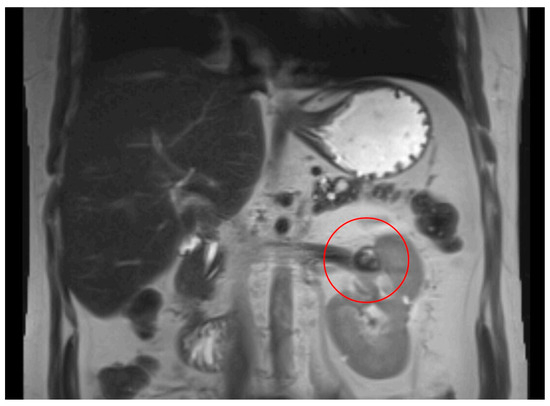

MRI abdomen scan, 6 February 2024, after 10 weeks treatment with belzutifan: regression of RCC.

2.3. Belzutifan in Von Hippel–Lindau-Associated Haemangioblastomas